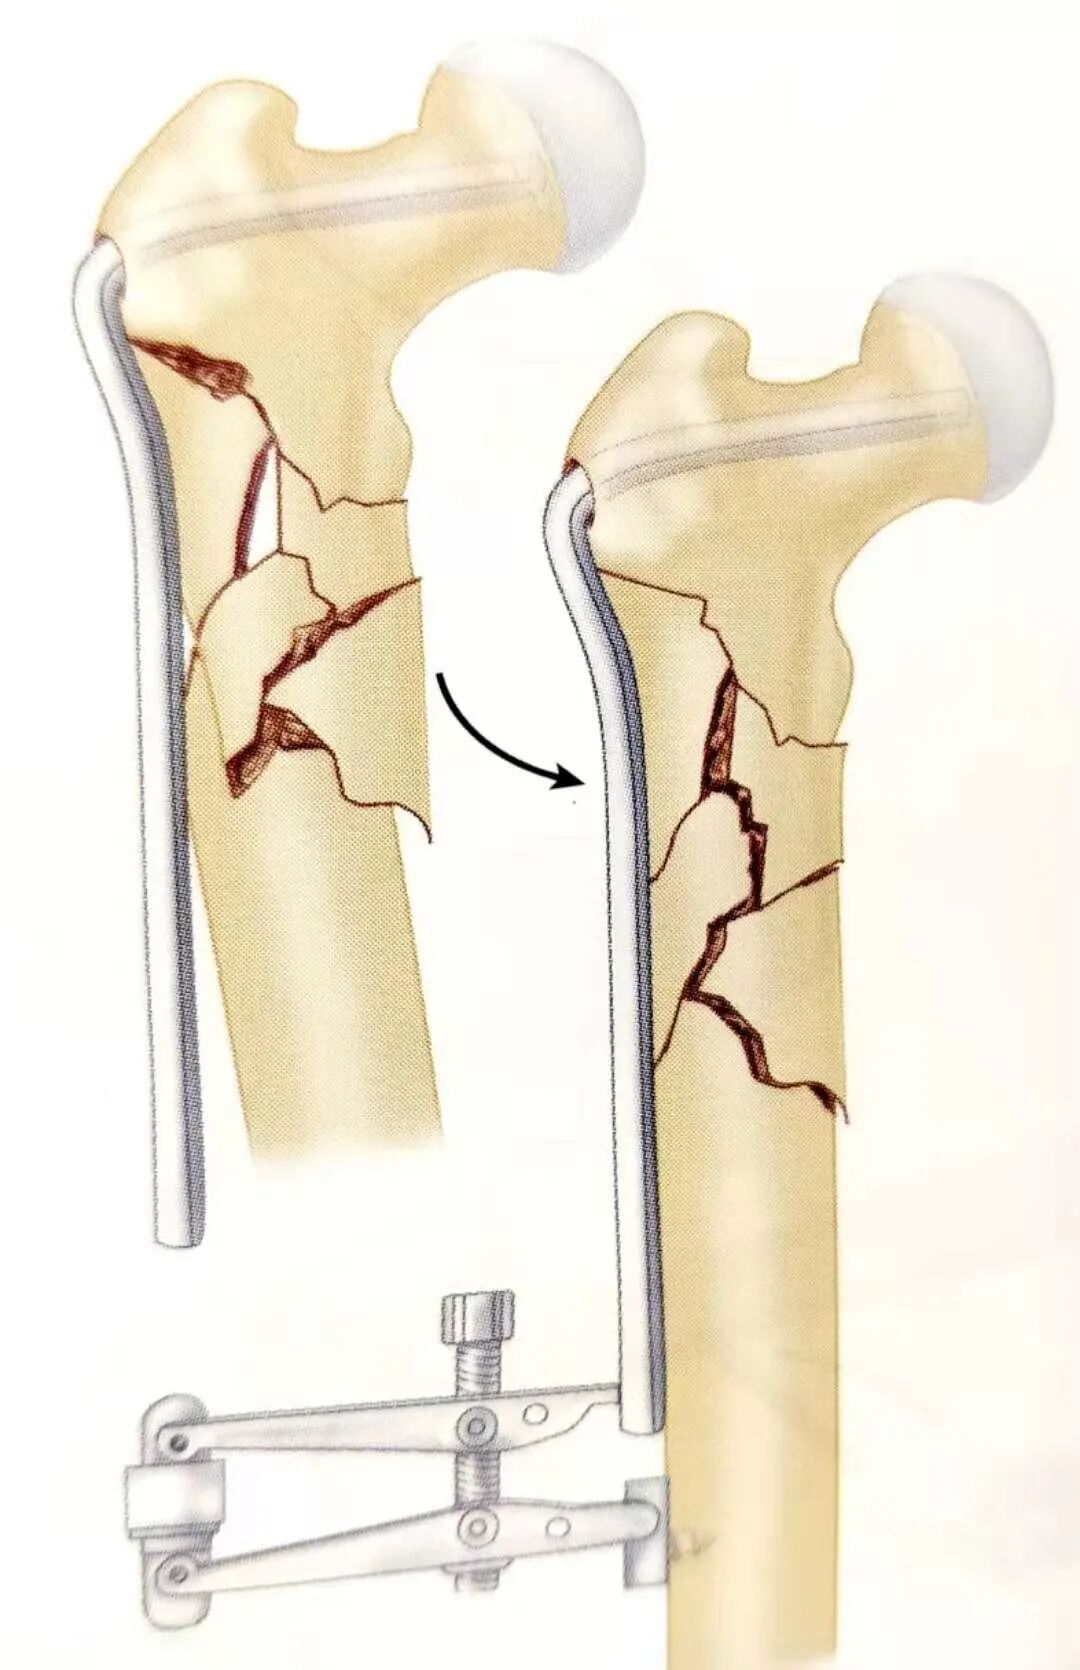

• 有时也可先将接骨板与近端固定,然后在接骨板远端的骨皮质上打入一枚螺钉,通过复位器牵拉接骨板的远端和更远端的固定螺钉,对骨折进行间接复位。

• 带关节的牵引器和椎板撑开器都可以用于作用于接骨板远端钉孔与远端皮质上的螺钉达到骨折的复位目的。

• 恢复长度后,纠正骨折的旋转,然后在骨折远端的钉孔内打入螺钉。

▲ 示意图